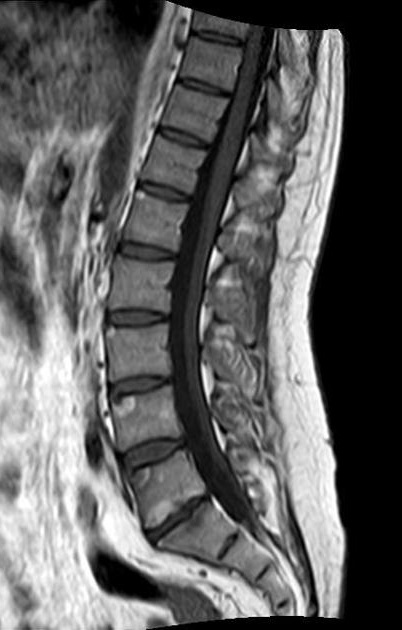

Image radiologique TDM en

coupe sagital d'une spondilite -ankylosant de D12

-L5 avec image de fracture du L1 . Image de

osteophyte anterieure du D12 et L2 avec image de

fibrose du ligament paras vertebrale anterieuse etre

en vue très nette |

Une autre cas de PSA du

thorax en association de lesion du corp

vestebrale.Image radiologique IRM en coupe sagital à

ponderation sur T1 |